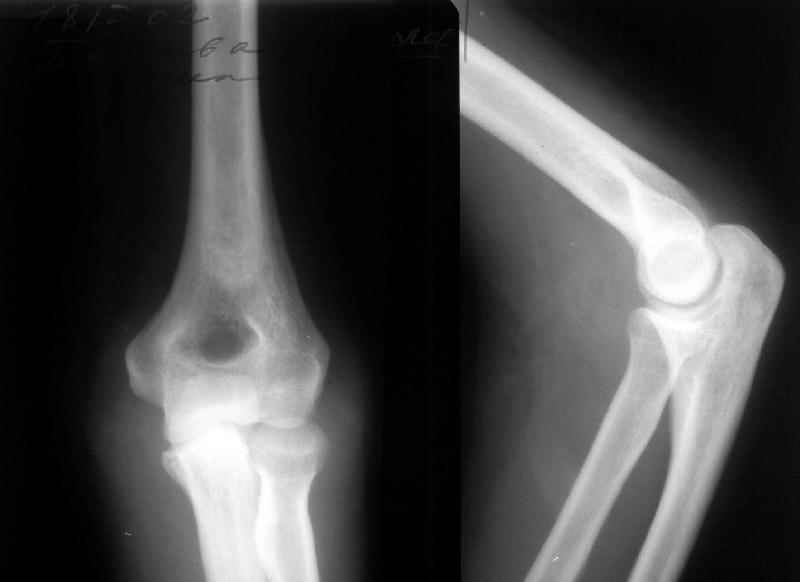

Кликните для загрузки файла flexion.jpg

31KB (32224 bytes)